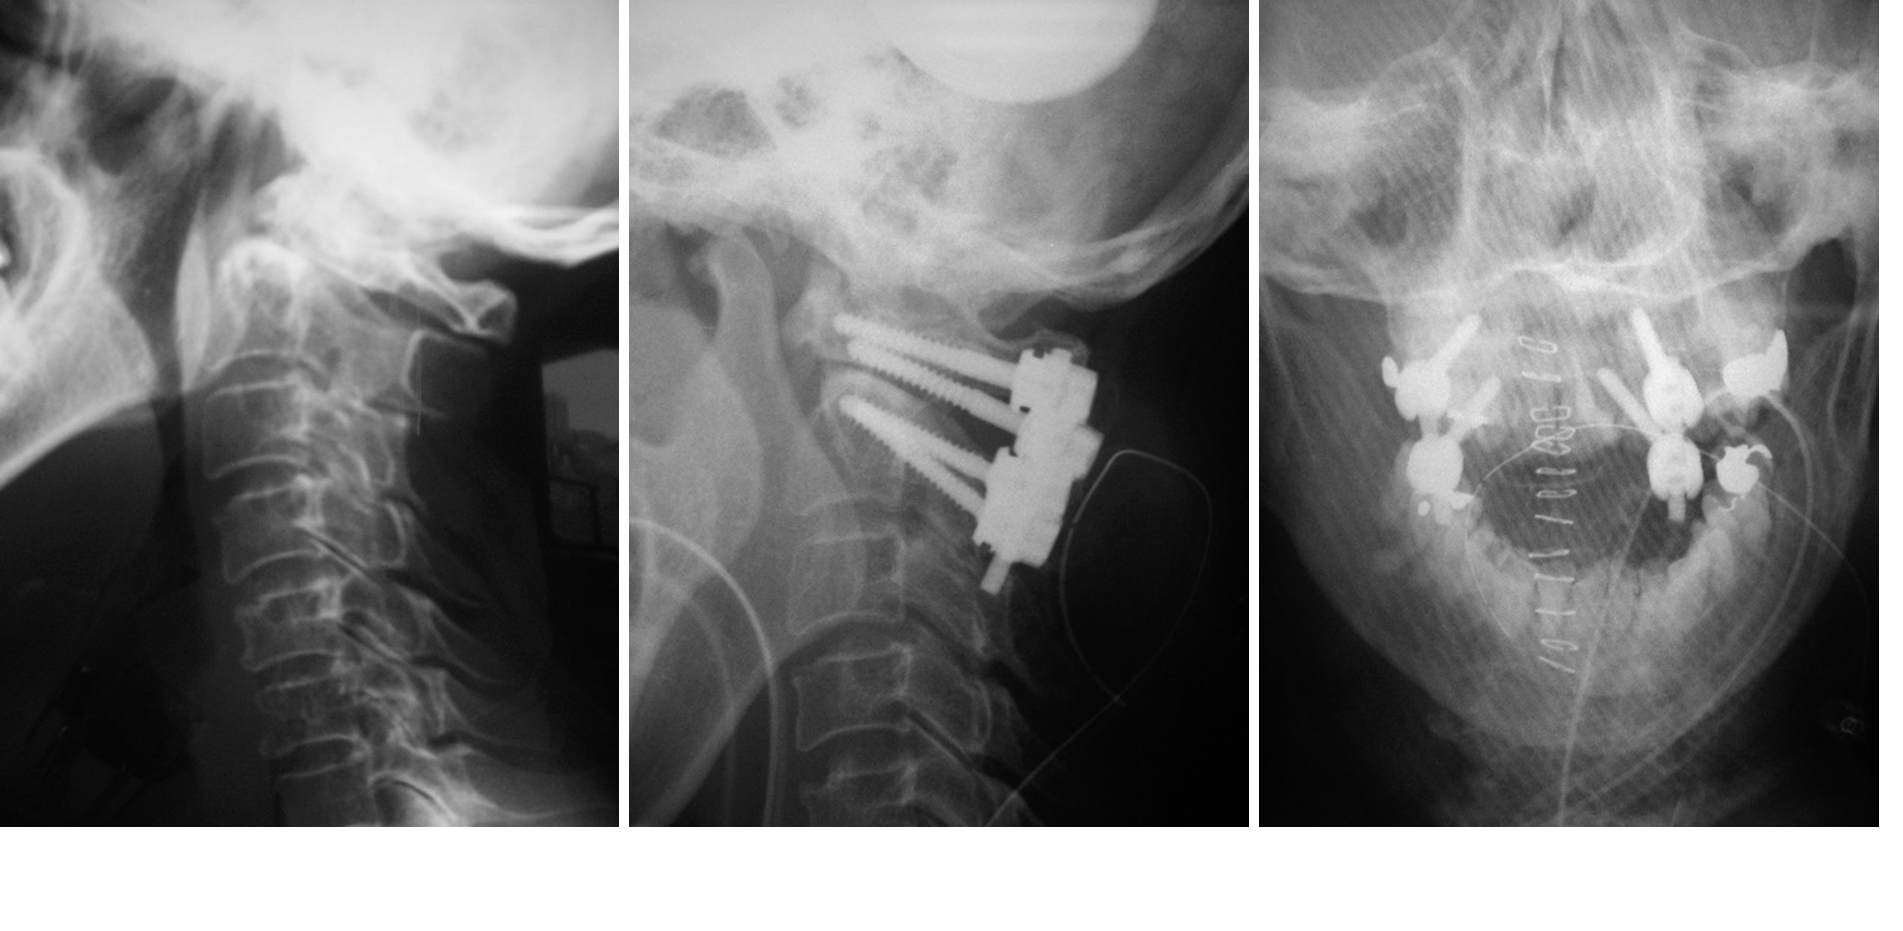

図 (左)歯突起骨により、第1-2頚椎のズレがみられます。

(まん中、右)第1-2頚椎がインプラントにより正常な位置に固定されています。